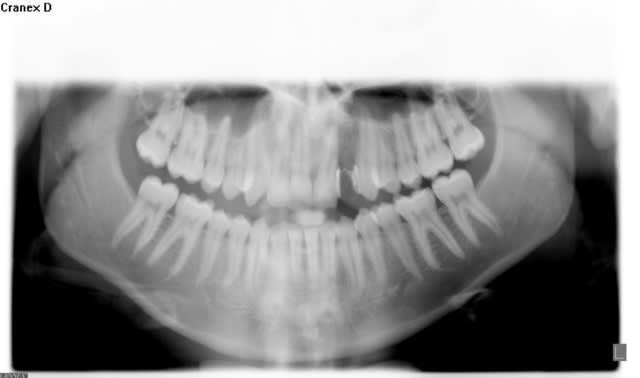

Pour dresser le tableau rapidement :

Patient de 21 ans ayant perdu une 22 lors d'un AVP en 2004. Tentative par un stomato de greffe en onlay de corail qui s'est soldée par un échec avec infection +++ et fonte osseuse aggravée.

D'après moi, dans ce cas, si on fait de la prothèse conventionnelle vu l'âge et vu la résorption osseuse au niveau de 21 et probablement 23, ça risque de ne pas durer éternellement. Sur le scan, il semble ne plus y avoir grand chose comme corticale vestibulaire.

Je suis trop peu compétent en chirurgie muco-gingivale à visée esthétique et en greffe osseuse pour me lancer dans ce cas, mais je pense qu'il faut se poser la question d'extraire 21 puis reconstituer la crête osseuse au niveau de 21-22 et gérer la hauteur de gencive kératinisée. Puis poser les implants... couronnes provisoires pour gérer les tissus mous puis prothèse définitive quand on est content du résultat.